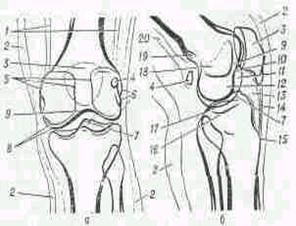

Рис 1. Строение колена.

Сустав колена - самый крупный сустав у человека. Он образован дистальным эпифизом бедренной кости и проксимальным эпифизом большеберцовой кости. По форме сустав колена относится к блоковидным суставам. Суставной конец бедренной кости состоит из двух мыщелков выпуклой формы. Суставная поверхность большеберцовой кости вогнутая. Однако несоответствие суставных поверхностей компенсируется наличием межсуставных хрящей - дисков. Медиальный мениск С-образной формы, а боковой - 0-образной. Мениски своими передними и задними рогами прикрепляются около мыщелковой возвышенности

Кроме того, передние рога соединены между собой поперечной связкой колена, а боковые поверхности - с капсулой сустава. Кроме крестообразных связок и менисков, сустав колена укреплен спереди сухожилием четырехглавой мышцы, которые ниже надколенника называют связкой надколенника. Часть пучков сухожильных волокон четырехглавой мышцы, идущих по боковым краям надколенника, прикрепляются к мыщелкам большеберцовой кости - медиальная и боковая поддерживающие связки надколенника. С боков сустав; колена укреплен двумя боковыми связками. Малоберцовая окольная связка начинается от бокового намыщелка бедра и прикрепляется к латеральной поверхности головки малоберцовой кости. Большеберцовая окольная связка начинается от медиального надмыщелка бедра, на уровне суставной щели срастается с капсулой сустава и медиальным мениском и прикрепляется к верхнемедиальной части большеберцовой кости. Разгибание в суставе колена осуществляется четырехглавой мышцей бедра, а сгибание - двуглавой мышцей бедра, полусухожильной и полуперепончатой мышцами.

Рис.2 Костные элементы коленного сустава. Правый коленный сустав.

1 - бедренная кость;

2 - надколенник;

3 - большеберцовая кость;

4 - головка малоберцовой кости;

5 - малоберцовая кость;

6 - боковой (латеральный) мыщелок.;

7 - наружная боковая связка коленного сустава;

8 - латеральный мениск (межсуставной хрящ коленного сустава);

9 - медиальный мыщелок коленного сустава;

10 - передняя крестовидная связка;

11 - внутренняя боковая связка коленного сустава;

12 - внутренний мениск (промежуточный диск коленного сустава;

13 - связка надколенника.

Внутри сустава расположены две мощные крестообразные связки колена. Капсула начинается в виде дуги на 0,5-1 см выше края хрящевой поверхности бедра, образуя впереди верхний заворот, переходит через сустав и прикрепляется к менискам, образуя боковые завороты. Спускается вниз и прикрепляется к большеберцовой кости, образуя передненижний заворот. Сзади капсула начинается по краю суставных поверхностей мыщелков бедренной кости, срастается с менисками и прикрепляется к краю суставной поверхности большеберцовой кости. На задней поверхности образуются задневерхний, задненижний, латеральный и медиальный завороты. Внутренняя поверхность капсулы выстлана синовиальным слоем, который с обеих сторон надколенника образует синовиальные крыловидные складки, включающие жировую клетчатку.

Рис 4. Правый коленный сустав вид сзади

1 - бедренная кость;

2 - надколенник;

3 - большеберцовая кость;

4 - головка малоберцовой кости;

5 - малоберцовая кость;

6 - боковой (латеральный) мыщелок.;

7 - наружная боковая связка коленного сустава;

8 - латеральный мениск (межсуставной хрящ коленного сустава);

9 - медиальный мыщелок коленного сустава;

10 - передняя крестовидная связка;

11 - внутренняя боковая связка коленного сустава;

12 - внутренний мениск (промежуточный диск коленного сустава;

13 - связка надколенника;

14. - задняя крестообразная связка.